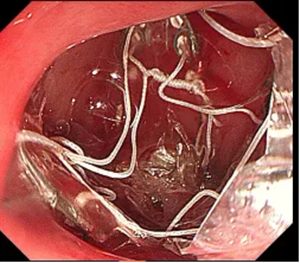

▲ 支架释放在肠道